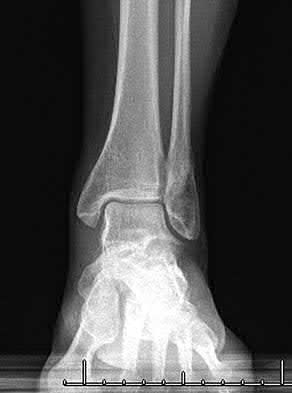

A 25-year-old female is involved in a motor vehicle collision. She presents with the isolated injury seen in Figures A through D. Her leg is swollen but her skin is intact. She has no clinical signs of compartment syndrome. Which of the following treatment options will allow for maintenance of fracture alignment and minimize the risk of soft tissue complications?

The patient presents with a closed distal third metaphyseal-diaphyseal distal tibia fracture with simple intra-articular extension. Immediate intramedullary nailing along with percutaneous fixation of the articular component provides appropriate restoration of length, rotation and alignment and minimizes the risk of wound complication.

Displaced distal third tibia fractures may be associated with simple intraarticular extension. Operative treatment of intra-articular distal tibia fractures has historically been performed with open reduction and internal fixation. Early open reduction and plate fixation of pilon fractures has been associated with high rates of infection and wound complication. In select patterns with simple articular extension, percutaneous screw fixation and medullary nailing may provide appropriate reduction with minimal soft-tissue risk.

Figures A and B demonstrate a distal third tibial shaft fracture with simple intra-articular extension. The axial and coronal CT cuts in Figures C and D further clarify the articular injury. Illustrations A and B demonstrate a comminuted distal third tibial fracture with simple intra-articular extension. Illustrations C and D are fluoroscopic images of the same injury after intramedullary nailing and percutaneous fixation of the articular component.